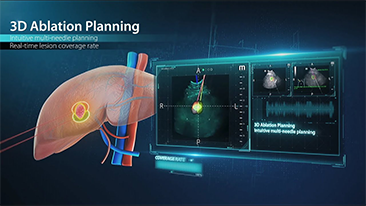

Mindray Resona General Imaging solutions help clinicians realize more accurate and efficient diagnosis and treatment results through comprehensive subdivision application probes and efficient clinical application tools.